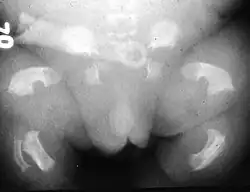

Radiogram of a baby born with thanatophoric dwarfism

Thanatophoric dysplasia is a severe skeletal disorder characterized by a disproportionately small ribcage, extremely short limbs and folds of extra skin on the arms and legs.

Infants with this condition have disproportionately short arms and legs with extra folds of skin. Other signs of the disorder include a narrow chest, small ribs, underdeveloped lungs, and an enlarged head with a large forehead and prominent, wide-spaced eyes. Thanatophoric dysplasia is a lethal skeletal dysplasia divided into two subtypes. Type I is characterized by extreme rhizomelia, bowed long bones, narrow thorax, a relatively large head, normal trunk length and absent cloverleaf skull. The spine shows platyspondyly, the cranium has a short base, and, frequently, the foramen magnum is decreased in size. The forehead is prominent, and hypertelorism and a saddle nose may be present. Hands and feet are normal, but fingers are short. Type II is characterized by short, straight long bones and cloverleaf skull.[1] It presents with typical telephone-handle shaped long bones and H-shaped vertebrae.

Infants with type 1 thanatophoric dysplasia also have curved thigh bones, flattened bones of the spine (platyspondyly) and shortened thoracic ribs. Note: Prenatal ultra-sound images of the ribs sometimes appear asymmetrical when in fact they are not. In certain cases, this has caused a misdiagnosis of osteogenesis imperfecta (OI) type II.